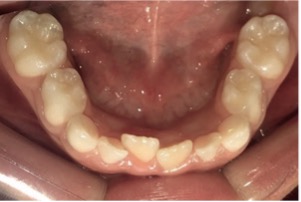

En el examen clínico intraoral, se observó dentición mixta, todos los dientes limpios, sin embargo, con maloclusión, por esa razón el paciente fue referido para evaluación y tratamiento ortopédico. Conforme la mamá había reportado, los incisivos laterales primarios inferiores estaban en oclusión (Figura 1) y sin movilidad. A través de la radiografía periapical en la región de los incisivos laterales inferiores (Figuras 2 y 3), fue observado que los gérmenes de los incisivos laterales inferiores permanentes se encontraban en la etapa 8 de Nolla, entonces, deberían estar estallando en la cavidad oral.

Figura 1: Fotografía intraoral oclusal de la arcada inferior: Se observa la presencia de los incisivos laterales primarios inferiores.